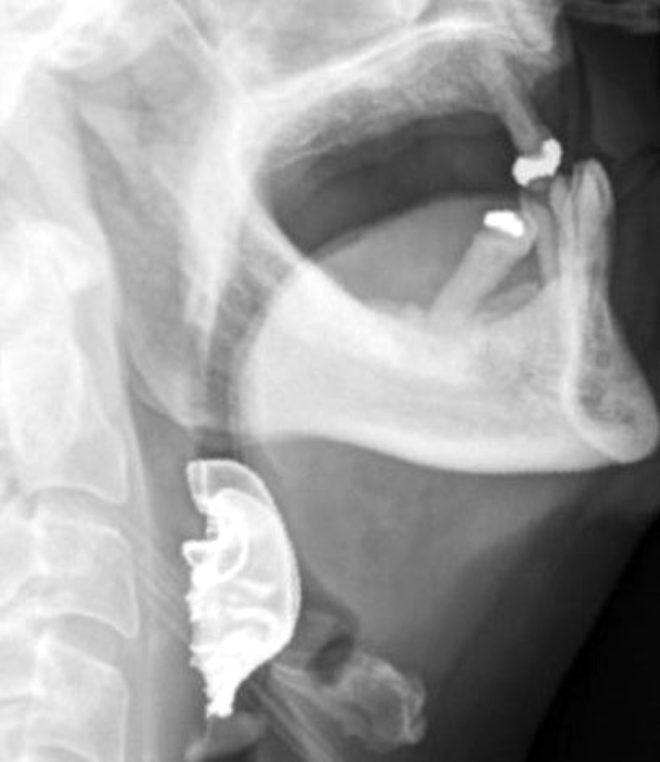

İngiltere'de bulunan bir üniversite hastanesinde ameliyat edilen 72 yaşındaki hasta, yutkunmada güçlük çekince skandal hata ortaya çıktı.

Hastanın boğazına kaçan takma dişleri, ameliyattan 8 gün sonra fark edildi.

Hasta, ameliyat sonrası yutkunmada sorun yaşadığından, öksürükten ve öksürükle birlikte kan tükürmekten şikayet etmeye başladı.